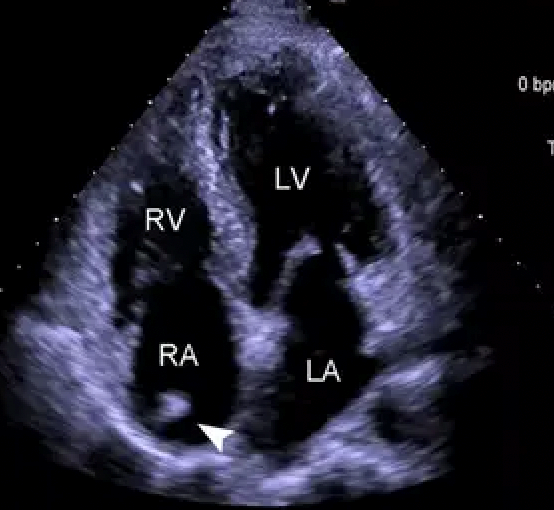

超声心动图

主要检查心脏各结构的解剖、位置、大小、形态与血流动力学是否正常,能测定心功能是否正常,了解心脏有无结构异常、房室大小异常,有无瓣膜病变、血流方向和速度异常,有无肿瘤、心包异常积液等。

能排查常见的疾病如高血压性心脏病、肺源性心脏病、风湿性心脏病、心功能不全、心脏瓣膜疾病(发育畸形、狭窄、关闭不全、脱垂、钙化、赘生物等)、升主动脉瘤/夹层、先天性心脏疾病(房缺、室缺、动脉导管未闭、肺动脉瓣狭窄等)、心肌病变(肥厚性心肌病、扩张性心肌病等)、心脏/心包肿瘤(粘液瘤、脂肪瘤等)、心包积液等。